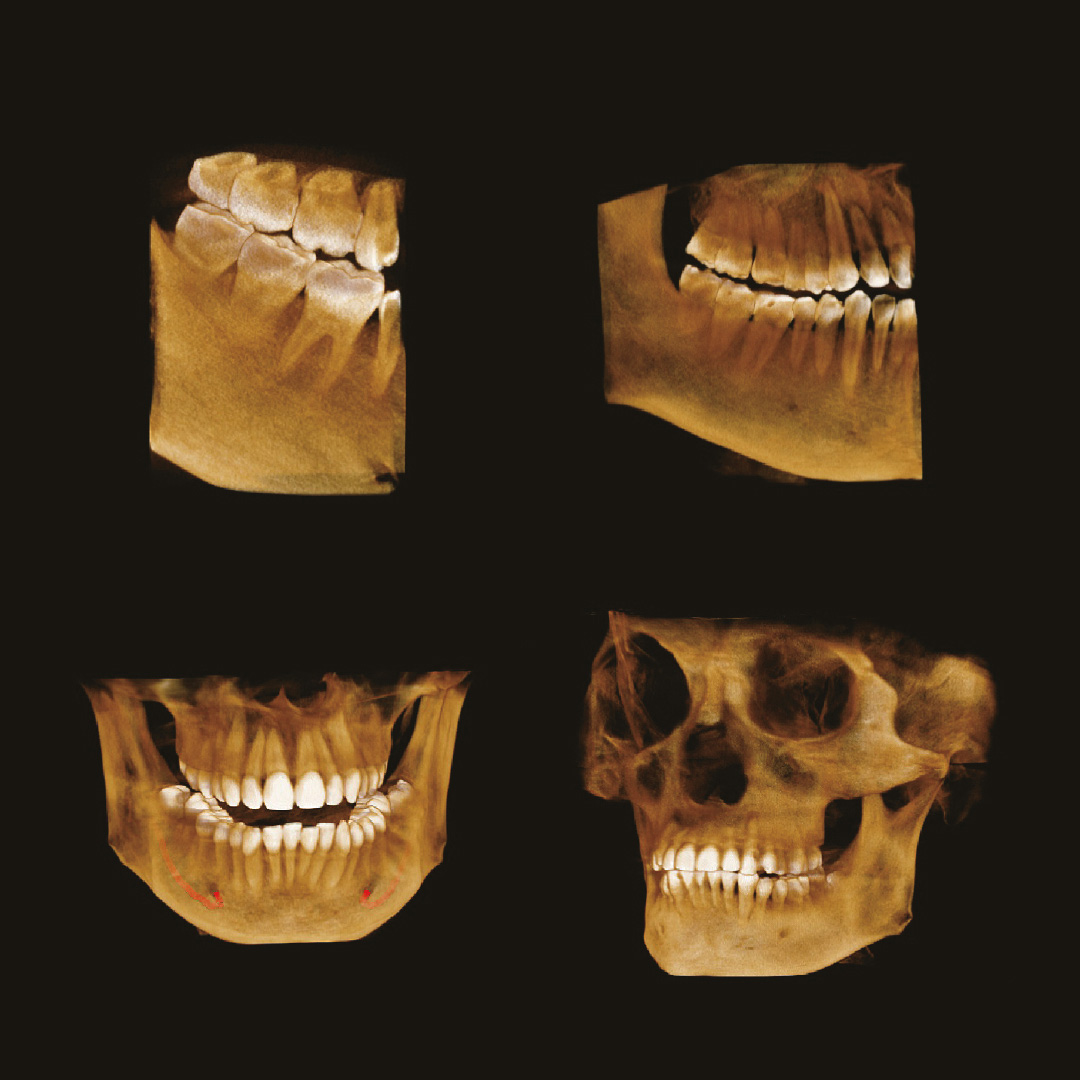

Стоматолог-хирург не способен производить свои манипуляции без снимка КТ, иначе он будет вынужден действовать вслепую, не сумев оценить анатомию области вмешательства.

Стоматолог-ортопед не сможет гарантировать надежность конструкции без правильной оценки стабильности опорных зубов при помощи снимка КТ.

Стоматологу-ортодонту, чтобы правильно простроить план лечения, помимо слепков, так же нужен снимок КТ.

Если же ваша стоматологическая клиника располагается в жилом доме, помимо всего написанного выше, необходимо, чтобы дентальный томограф имел мощность излучения не выше 70кВ. Современные изготовители позаботились и об этом. На рынке представлено несколько моделей, которые удовлетворяют этим требованиям. Например, модель дентального томографа Papaya 3D (Plus) от компании Genoray имеет мощность излучателя 60~69 кВ и может располагаться в жилых помещениях, не принося вред жильцам и удовлетворяя санитарно-эпидемиологическим требованиям.